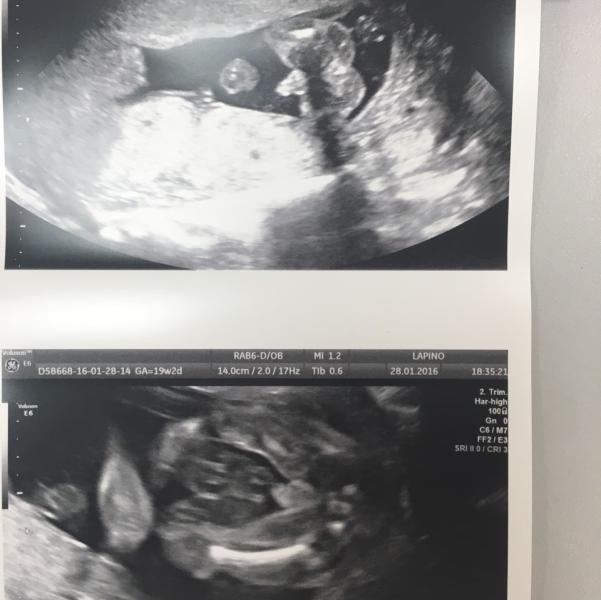

Врач, у которого наблюдаюсь, сказал, что у меня будет девочка. А поехала в Лапино сказали мальчик. Блин. Кто из них прав) вот узи из Лапино

Лапино очень понрав! Думаю там рожать. Приём первый бесплатно. А так 6.500₽, за узи заплатила 6.500₽ (обычно это 2-4.000₽ стоит) Но уровень конечно топ!!

точно парень у Вас))) у девочек там персик и все плоско почти)

Я сначала фото посмотрела. Думаю: "мальчик на узи". А потом уже вопрос прочитала. Так что я тоже за мальчика)

А я вижу половые губы, как на УЗИ девочек, а "пенисом" может быть пуповина 😜 мой голос за девочку. ну хотя бы для разнообразия)